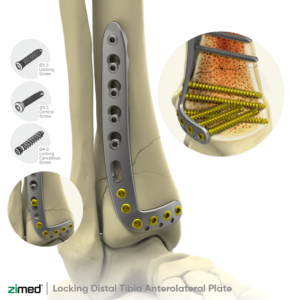

Locking Distal Anterolateral Tibial Plate

-